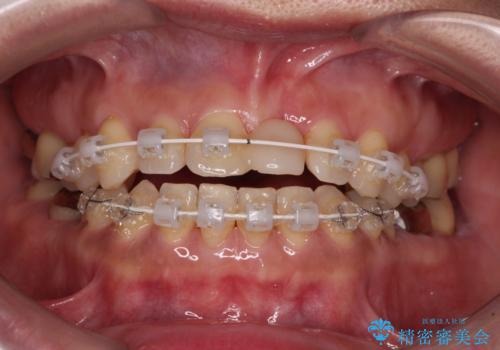

中途半端な矯正治療と前歯の欠損 再矯正とオールセラミッククラウンによる補綴治療

- 矯正治療を行ったものの、隙間やデコボコが多く、欠損している前歯も気になるとのことで来院された患者様です。

当初はセラミック治療だけを希望されていましたが、上下前歯のデコボコが顕著であったため、セラミッククラウンにて治療する前に再度矯正治療を行った方が仕上がりがきれいになると説明し、再矯正を行うこととしました。